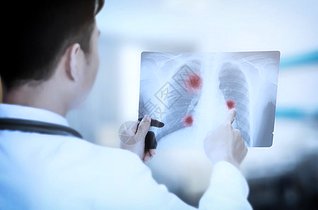

看胸片素材 看胸片高清图片 摄图网图片下载

摄图网为您找到关于看胸片图片素材正版可商用图片结果共计:187746张,您还可以找到:看胸片背景图片、看胸片海报模板、看胸片插画、看胸片元素图片、看胸片朋友圈说说配图、看胸片gif 动图...